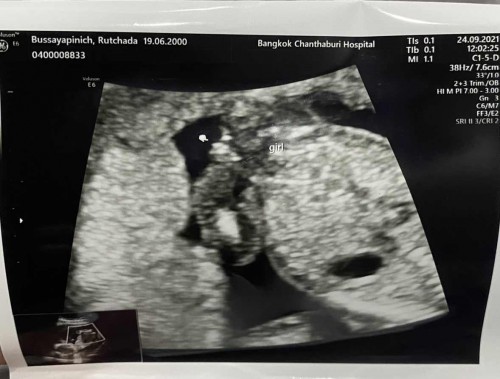

ลูกสาวหรือลูกชาย

สอบถามแม่ๆค่ะ ซาวด์ตอน 16w หมอบอกน่าจะเป็นผู้หญิง ยังไม่ชัวร์ เพราะน้องอยู่ไม่ค่อยนิ่ง แม่ๆคิดว่าญหรือชคะ👧🏻👶🏻#ขอบคุณสำหรับคำตอบค่ะ

บ้านนี้ตอนซาวเพศครั้งแรกตอน16วีคเห็นไม่ชัดเท่าไหร่หมอบอกว่าน่าจะเป็นผู้หญิงค่ะแม่แต่ไปซาวมาตอน20วีคเห็นชัดมากค่ะจิมิอันน้อยๆ

มองไม่ชัดเหมือนกันค่ะ ถ้าให้ชัวร์ 20 week หมอน่าจะดูให้อีกทีค่ะ

น่าจะญ